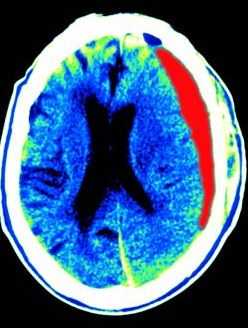

КТ головного мозга. Кровоизлияние в мозжечок.

Кровоизлияние в мозжечок является следствием гипертонии и составляет около 10% всех случаев кровоизлияний в мозг. Обширное кровоизлияние может вызвать обструкцию 4 желудочка и гидроцефалию. Ранняя диагностика обычно осуществляется с помощью КТ. При МРТ головного мозга уже на вторые - третьи сутки кровь становится гипоинтенсивной на Т2-зависимых МРТ за счет превращения оксигемоглобина в дезоксигемоглобин. Эритроциты остаются неразрушенными. Дезоксигемоглобин на Т1-зависимых МРТ изоинтенсивен белому веществу. Процесс изменения гемоглобина идет снаружи внутрь, поэтому внутримозговое кровоизлияние имеет кольцевую структуру. На Т2-зависимых МРТ снаружи идет широкая зона гиперинтенсивного отека, в центре - резко гипоинтенсивное кольцо внутриэритроцитарного дезоксигемоглобина. Уже на 5-6 сутки дезоксигемоглобин превращается в метгемоглобин, который гиперинтенсивен на МРТ обоих типов зависимости.